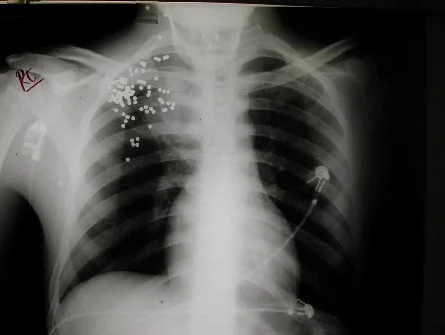

Shotgun pellets 1

Shotgun pellets 2